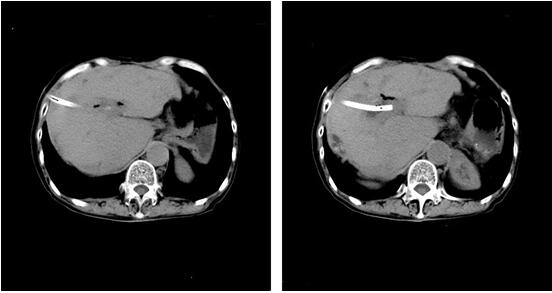

更不幸的是,今年年初,周某复查发现肝内胆管结石又复发了。周某采用保守消炎治疗,短短半年时间,反复寒战,发烧,肚子痛5次,并且眼睛和皮肤越来越黄。为求治疗收入我院。入院后完善腹部CT检查,发现周某肝内胆管又长了许多结石,主要集中在肝门胆肠吻合口附近和左边肝内胆管,导致肝内胆管明显扩张(见图1)。当我们和周某商量下一步治疗方案的时候,周某说自己做了4次开刀手术,非常惧怕再次开刀。我们深表同情,有没有办法不开刀,肚子上打个小洞就能取出肝内胆管的结石呢?

图1 患者术前CT检查。肝内胆管多发结石(已标记),最大直径约3厘米,肝内胆管扩张和积气。